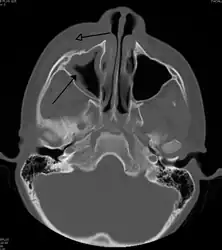

If the diagnosis is unclear, a CT scan may be done to rule out other possibilities.

Periorbital cellulitis caused by a dental infection (also causing maxillary sinusitis)